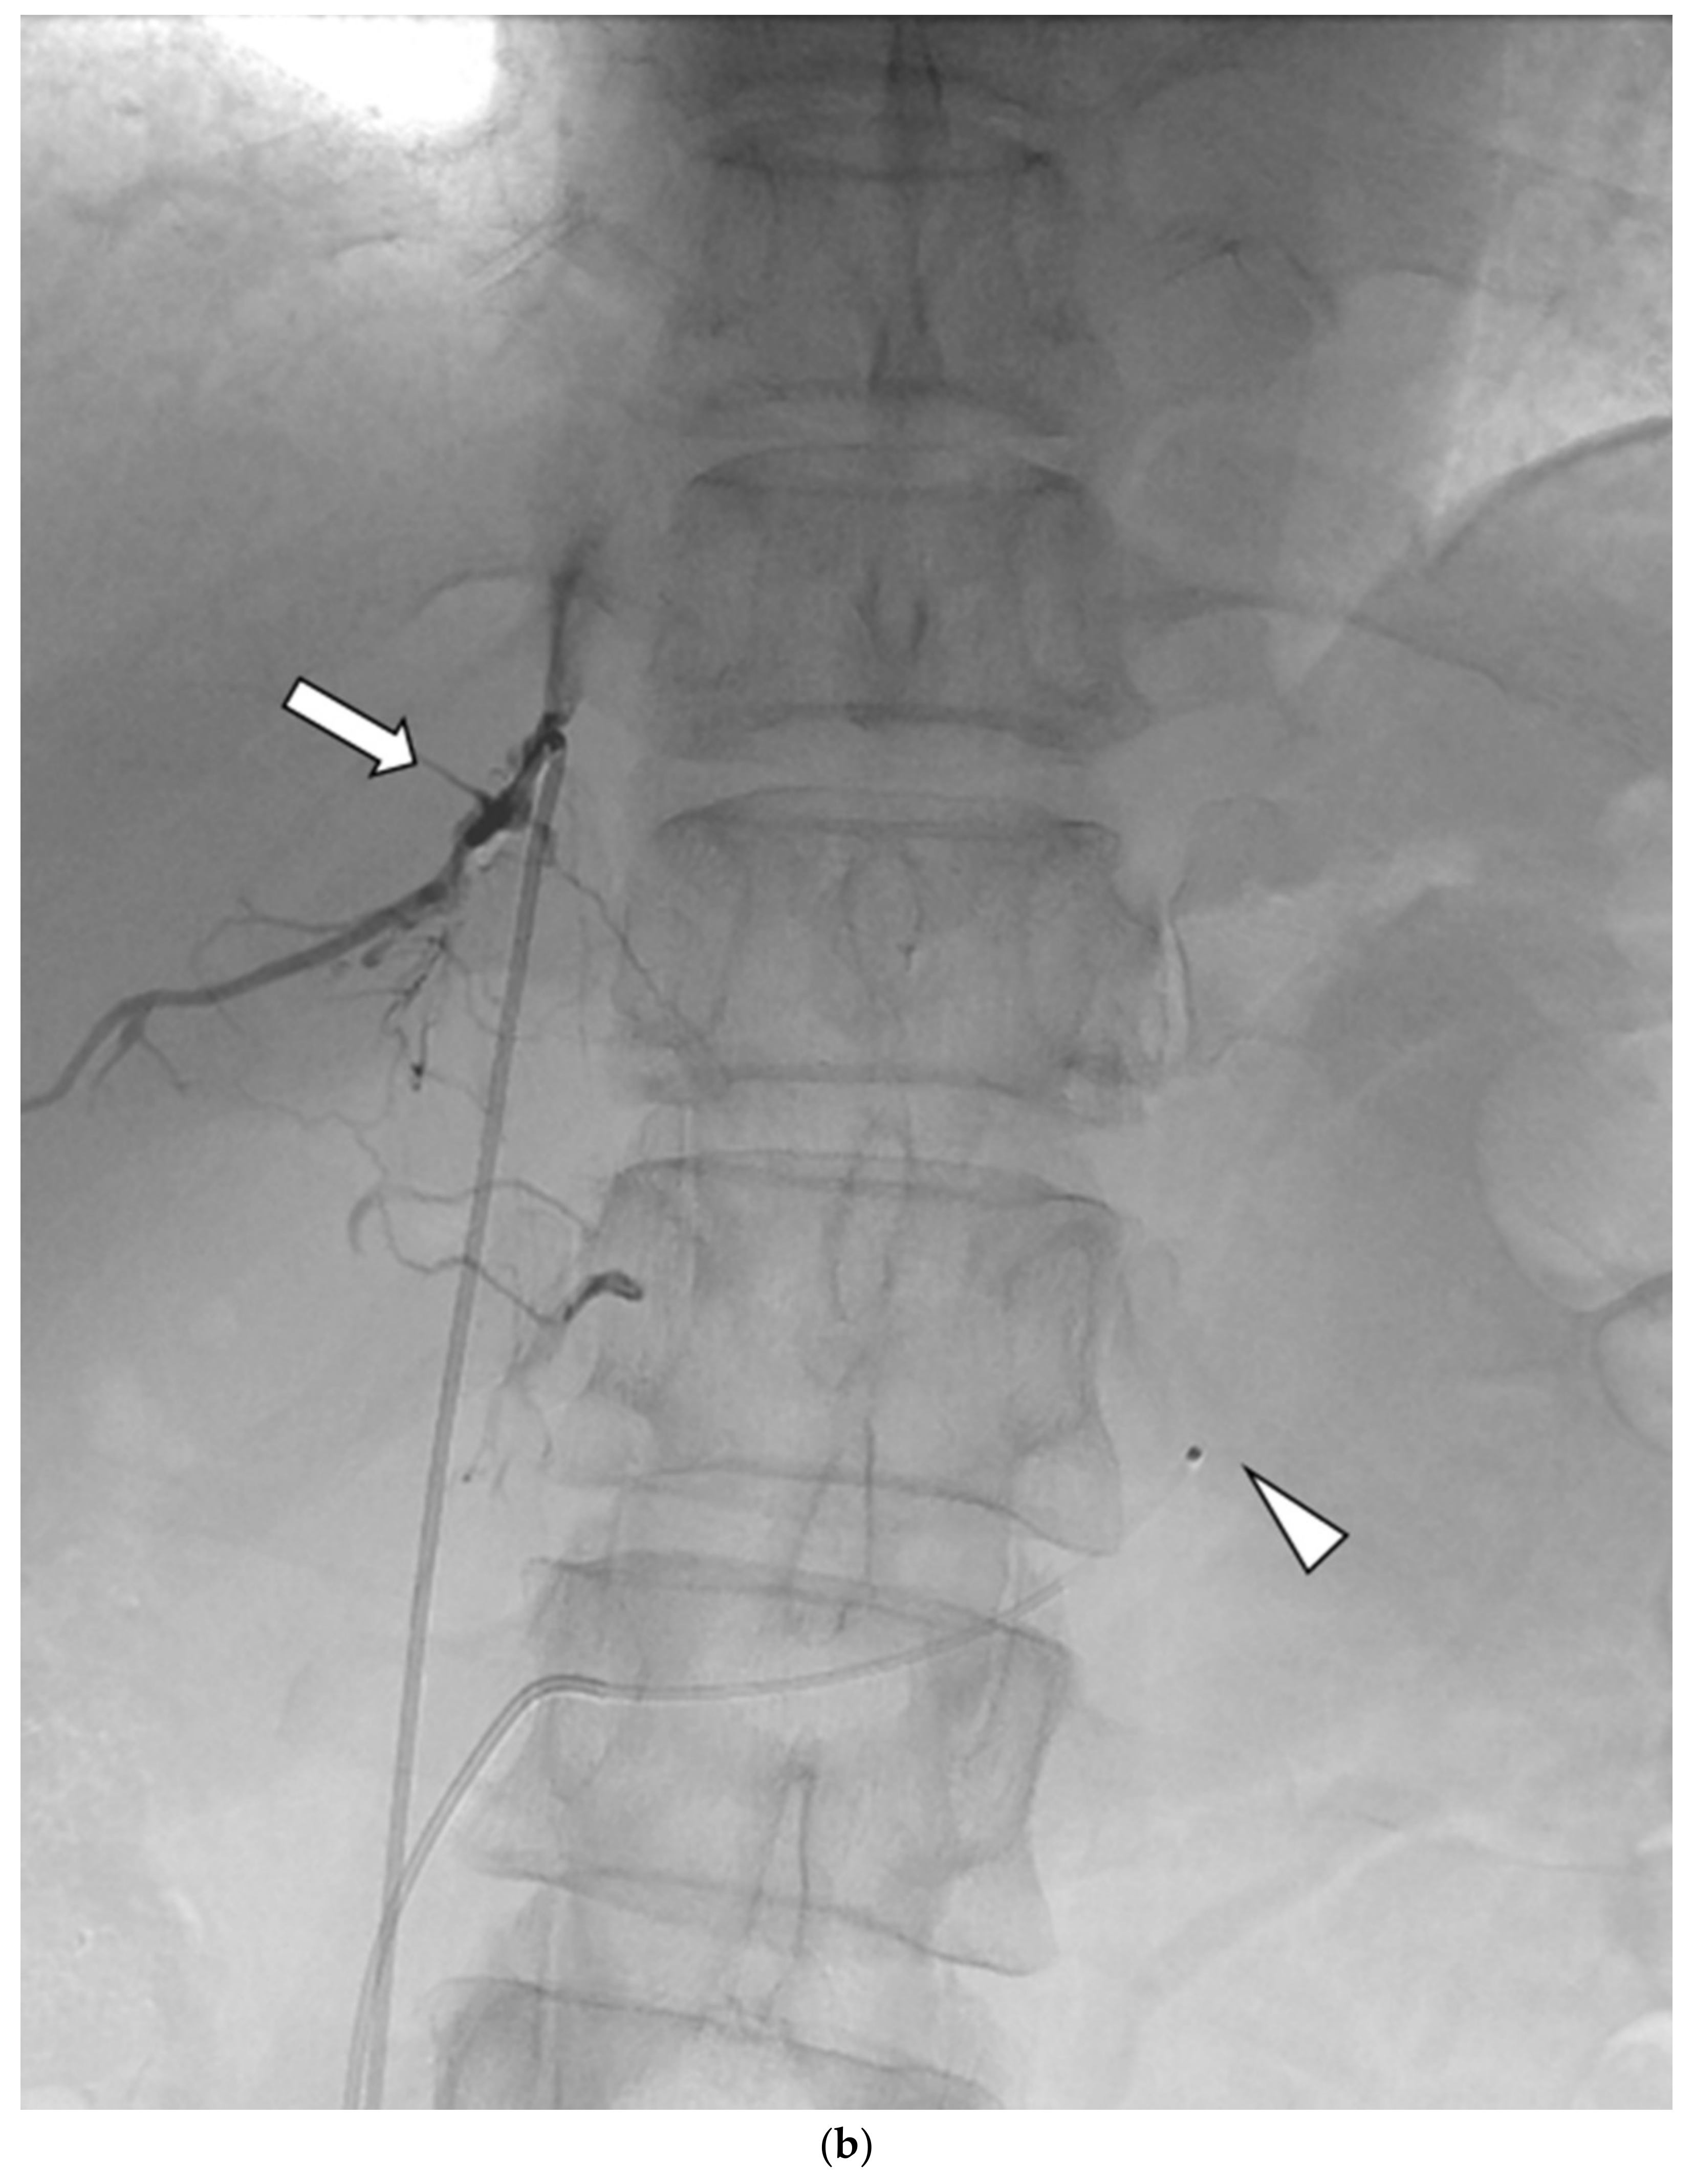

An Ancillary Method for Adrenal Venous Sampling in Cases in Which Right Adrenal Vein Sampling Is Difficult

2.2. AVS Procedure